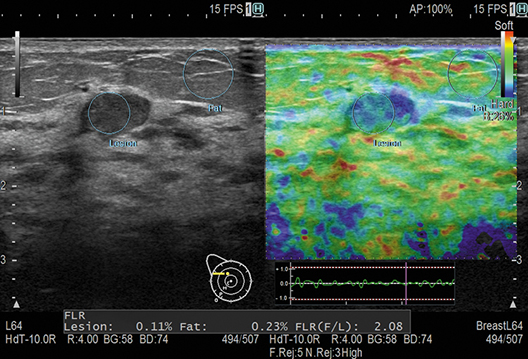

Auto Frame Selection (AFS) picks out the appropriate frame for measurement in Real-time Tissue Elastography. Assist Strain Ratio (ASR) automatically locates the measurement ROI. Complex, repetitive measurement steps can now be completed using a single button.